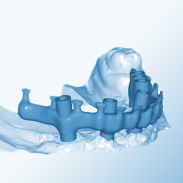

Unter einem Implantat versteht man eine künstliche Zahnwurzel, die von einem Implantologen in den Kiefer eingesetzt wird. Für dieses Implantat werden künstliche Zahnpfeiler hergestellt, sogenannte Abutments, für die dann der eigentliche Zahnersatz konstruiert und angefertigt wird. Die Verbindung zwischen Implantat und Abutment erfolgt durch eine Verschraubung.

Man unterscheidet zwischen festsitzendem Zahnersatz (Kronen und Brücken) und herausnehmbarem Zahn-

ersatz (Totalprothetik oder als Kombination).